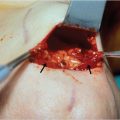

The marked skin and subcutaneous tissue are excised above the musculo-aponeurotic tissue. The galea and the periosteum are bluntly separated with a closed hemostat dissecting along the muscle fibers to avoid damage of the local sensory nerves. Using a curved periosteal elevator, the subperiosteal dissection extends to the supraorbital rims and to the frontotemporal line (Fig. 21‑3). Dissection is extended to the nasal tip to release the procerus. Direct visualization is obtained using a lighted rigid endoscope (Fig. 21‑4) and endoscopic video monitor (Fig. 21‑5). An optical cavity is created using a sheath around the scope to elevate the soft tissue off the lens. In addition, three nylon suspension sutures are placed externally just above the brow line (Fig. 21‑6). Divergent traction is placed on the sutures. The traction on the sutures helps create an optical cavity.